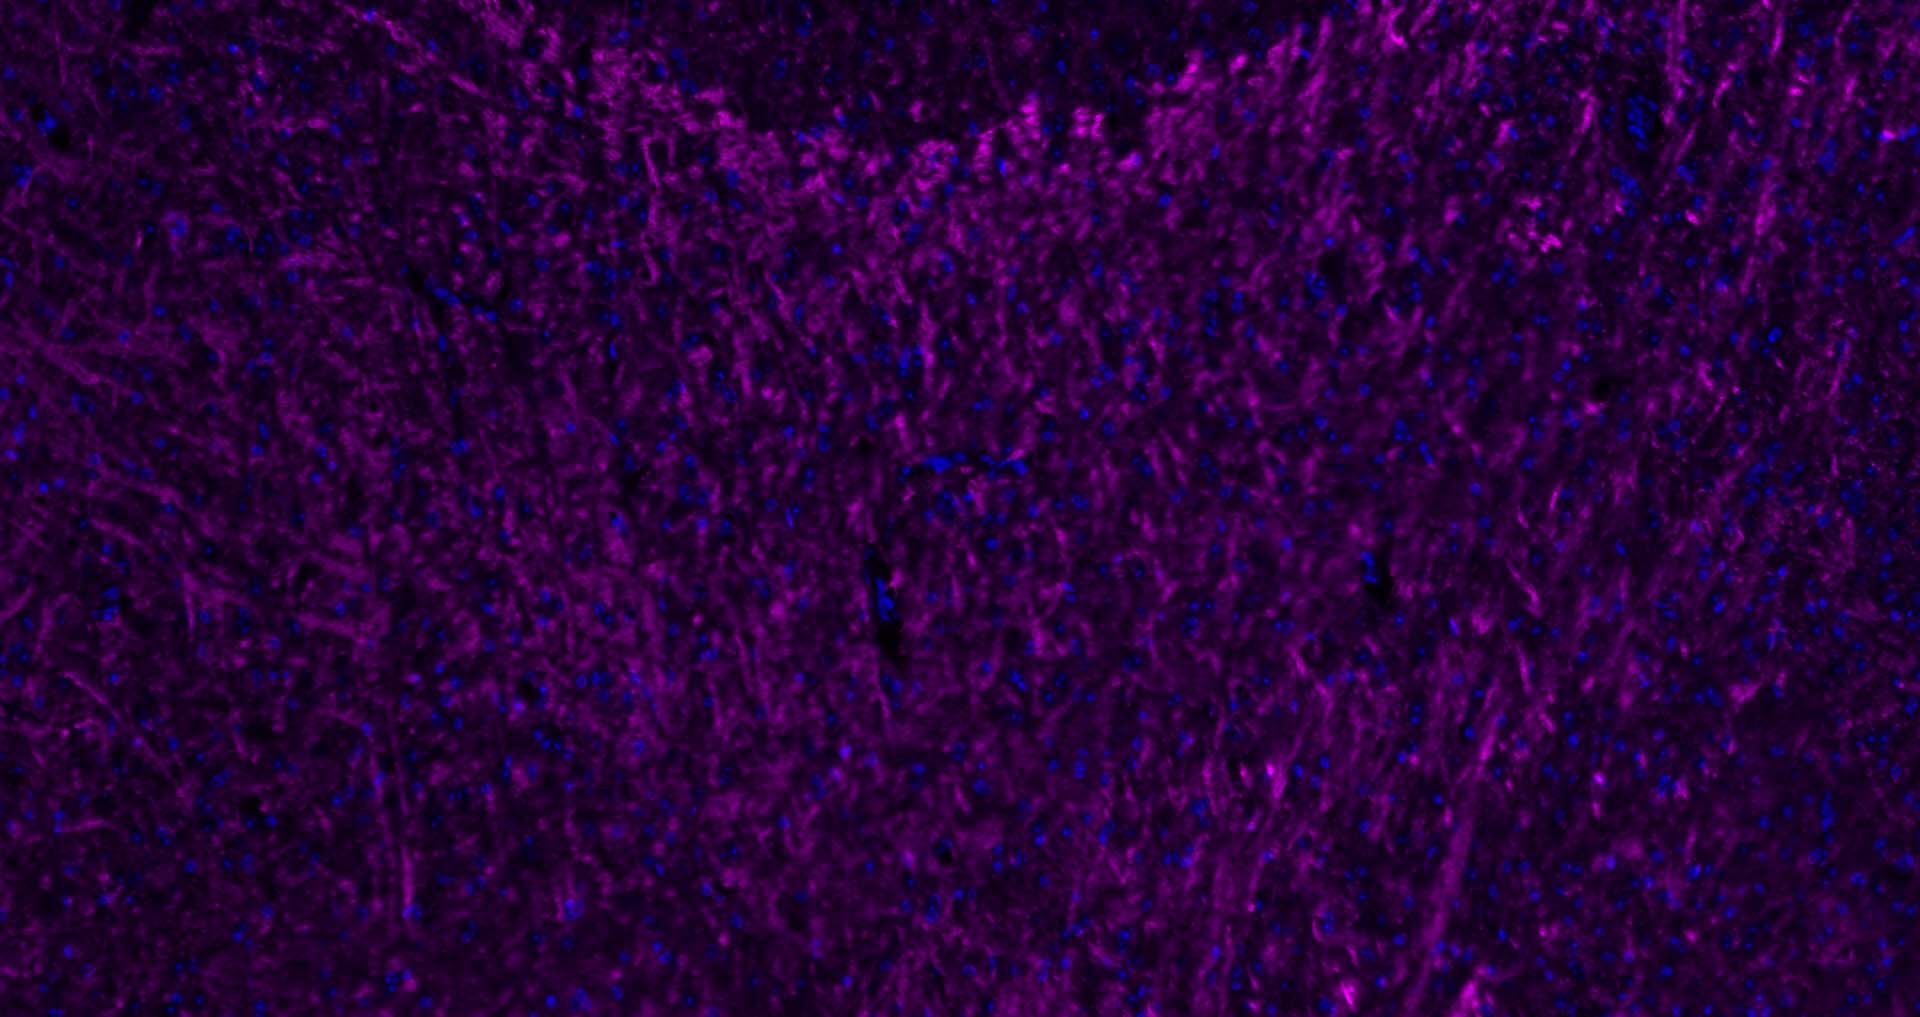

The protein encoded by the classic MBP gene is a major constituent of the myelin sheath of oligodendrocytes and Schwann cells in the nervous system. However, MBP-related transcripts are also present in the bone marrow and the immune system. These mRNAs arise from the long MBP gene (otherwise called "Golli-MBP") that contains 3 additional exons located upstream of the classic MBP exons. Alternative splicing from the Golli and the MBP transcription start sites gives rise to 2 sets of MBP-related transcripts and gene products. The Golli mRNAs contain 3 exons unique to Golli-MBP, spliced in-frame to 1 or more MBP exons. They encode hybrid proteins that have N-terminal Golli aa sequence linked to MBP aa sequence. The second family of transcripts contain only MBP exons and produce the well characterized myelin basic proteins. This complex gene structure is conserved among species suggesting that the MBP transcription unit is an integral part of the Golli transcription unit and that this arrangement is important for the function and/or regulation of these genes.

| IF | Human, Mouse, Rat | Rabbit, Pig, Sheep, Cow, Dog, Horse | 1:500-2000 |